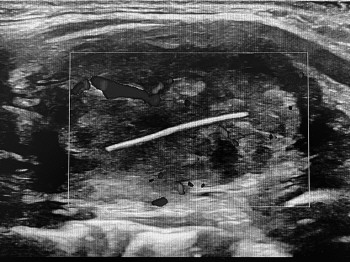

于是,童童的父母将他带到滨州医学院附属医院就诊。当时,童童甲状腺肿大明显,并伴有压痛,可触及颈部淋巴结肿大。经彩超检查提示甲状腺异物伴周围炎症可能。考虑异物穿过食道刺入甲状腺中,引起化脓性甲状腺炎。患儿持续发热,颈部肿痛明显,不及时救治可能致脓毒血症,危及生命,手术迫在眉睫!

甲状腺外科副主任韩勇立即请儿外科、儿童消化与肾病科、超声医学科、放射科等科室会诊,经多科专家讨论后,制定了周密的手术方案。由于患儿甲状腺异物为青小麦芒,异物质地较柔软,手术中不易寻找,常规手术方案一般选择甲状腺患侧腺叶切除。但患者年龄较小,切除过多甲状腺组织可能导致甲状腺功能低下,影响患儿发育。因此,计划手术中在超声定位下将注射器针头刺入甲状腺,直至麦芒尖端。然后剖开甲状腺腺体,沿针头寻找异物。

手术由甲状腺外科武孟孟主治医师与安兴国主治医师共同完成,术中在彩超医师彭振翼协助下,按术前计划缜密实施。术中“针尖对麦芒”,通过注射器针头,精准定位麦芒,完整取出异物,最大限度保留了患儿的甲状腺组织。患儿术后恢复良好,术后4小时正常进食,颈部疼痛明显改善,未再出现发热,3天后拔除引流管,康复出院。